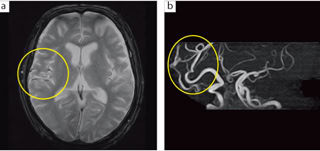

当院のMRIは閉塞感の少ないオープンタイプのMRI機器を設置しています.可能な限り受診当日にMRIを撮影し,大きなモニターに表示して結果を説明します.

MRI Aperto Eterna(0.4Tesla, OpenMRI)